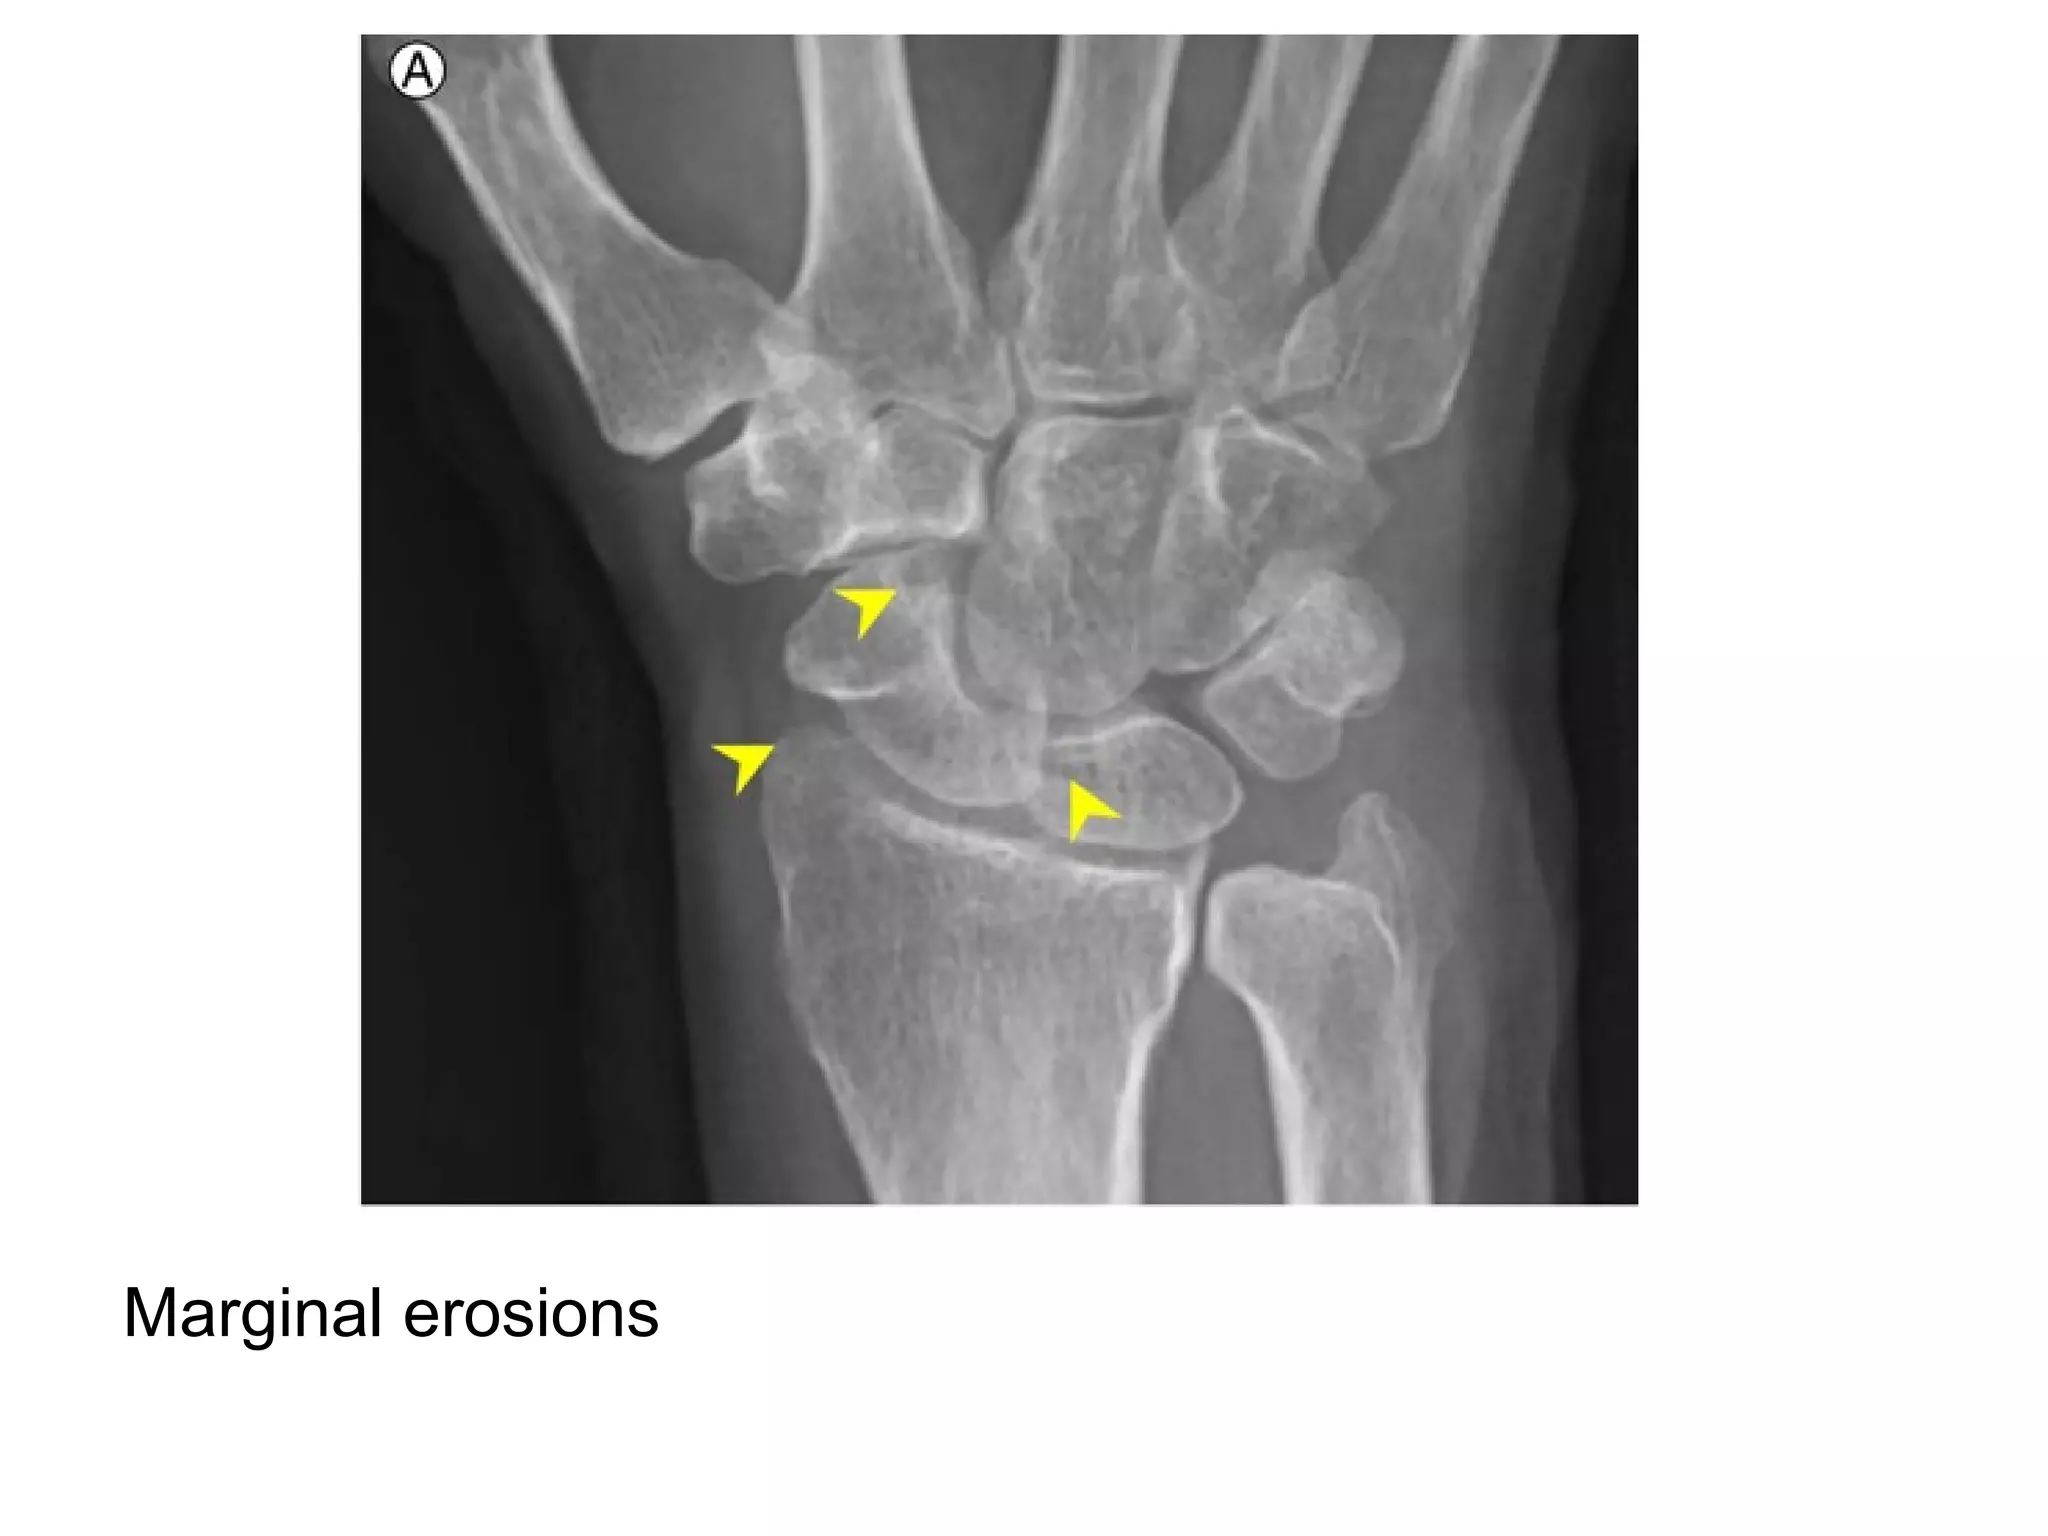

Marginal erosions

Advanced changes of rheumatoid arthritis with soft tissue swelling (yellow

arrows) , narrowing of the radiocarpal joint space (blue arrow) , erosions

(red arrows) and destruction of the ulnar styloid (green arrow) , the

intercarpal joints are destroyed as re all of the carpal-metacarpal joints of

both hands , note the symmetric appearance of the disease